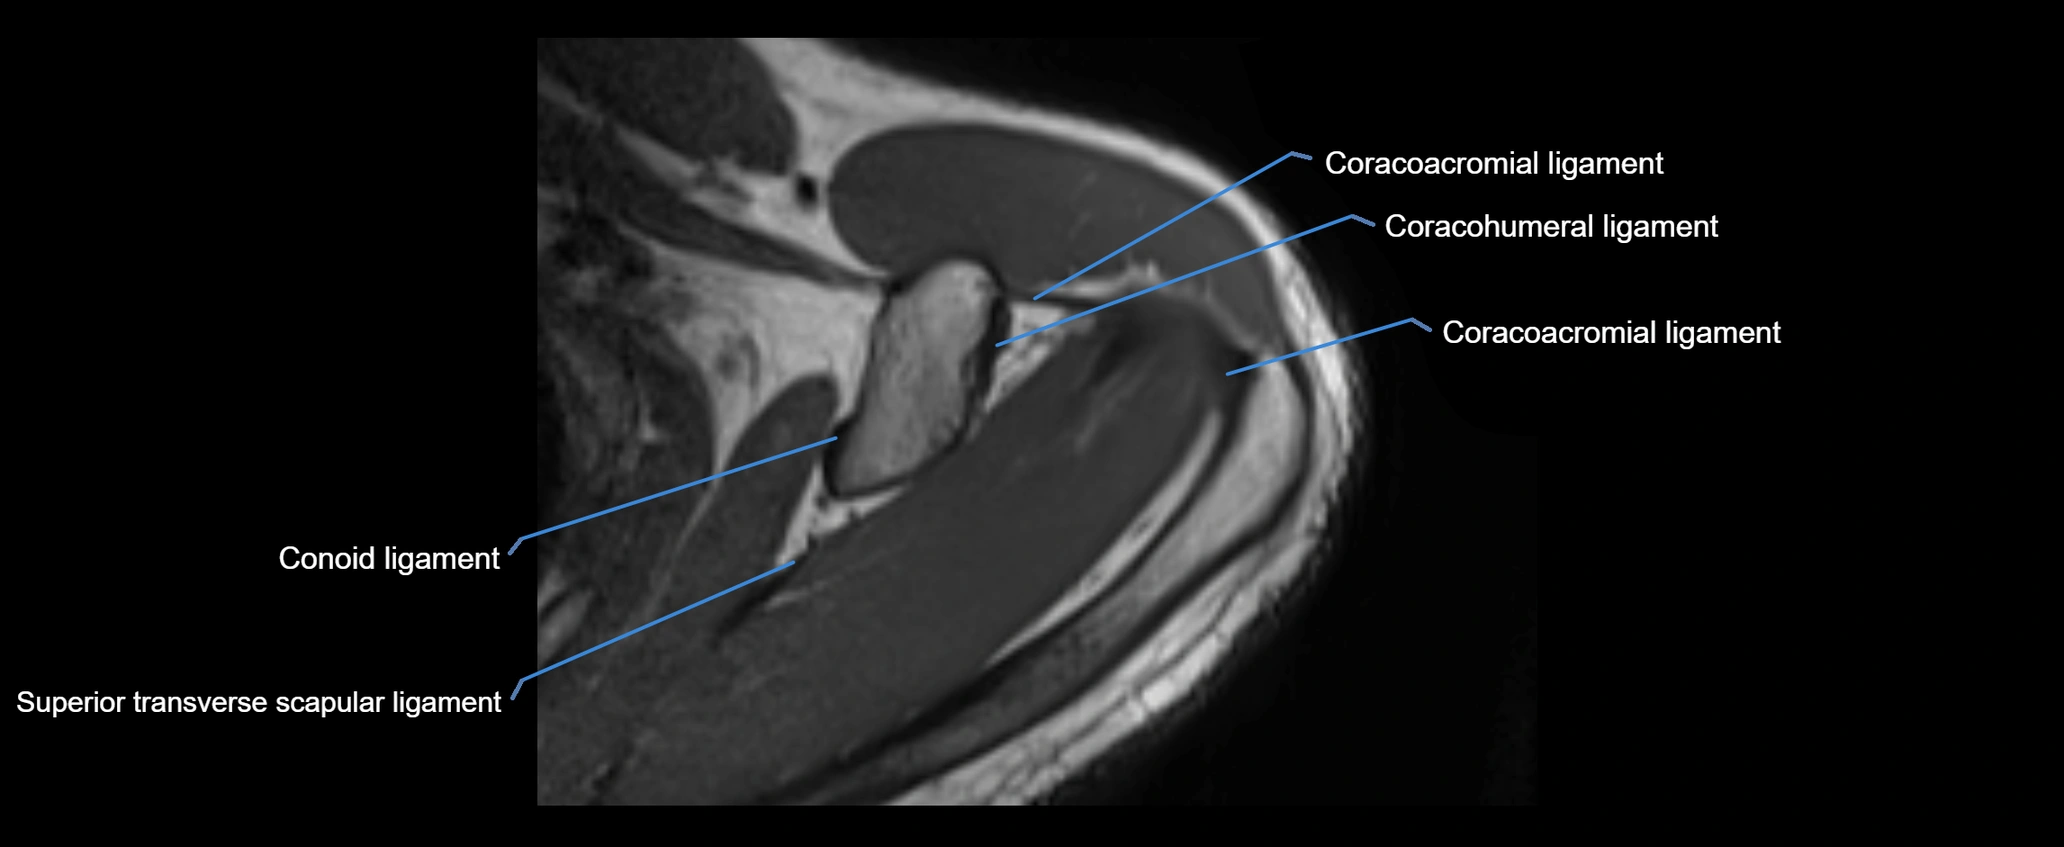

MRI images

image